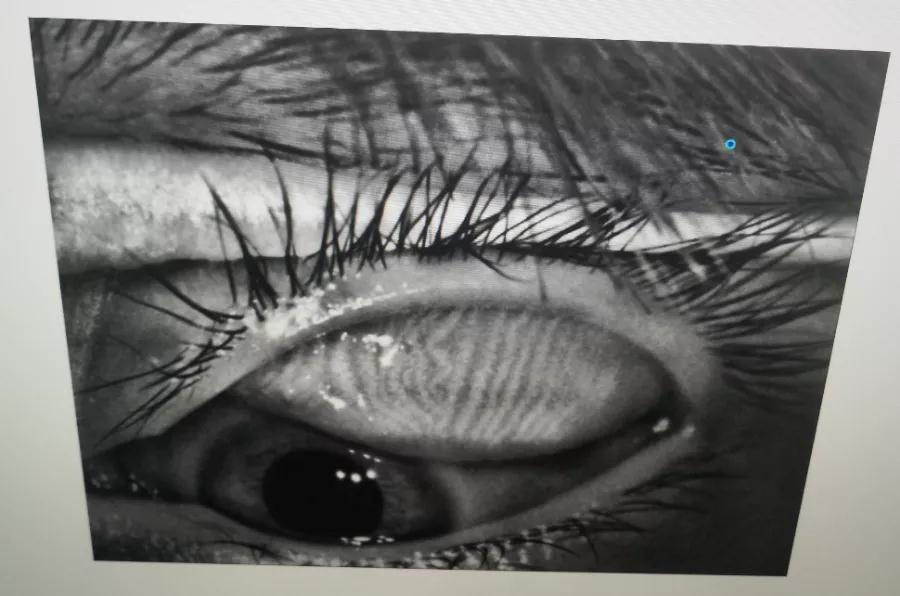

瞼板腺是排列在我們上下眼皮里面,分泌油脂的腺體,這些油脂是組成淚液的重要成分,可以讓淚水更長時間的停留在眼球表面。瞼板腺油脂減少,淚水蒸發(fā)就會加快,眼球暴露在外的時間變長,會加重眼睛干澀,時間一久,干眼也就隨之而來。

通過熱敷并按摩擠壓上下眼瞼,將瞼板腺內(nèi)不能自行排出的分泌物推出,疏通堵塞的瞼板腺開口。

熱敷可以促進(jìn)眼周部位的血液循環(huán),瞼板腺按摩能有效改善瞼板腺功能,解決絕大多數(shù)干眼患者油脂分泌不足問題。

03、OPT強脈沖光

通過強脈沖光高溫消除蠕形螨蟲,同時脈沖光產(chǎn)生的熱量可以熔解軟化瞼酯,改善瞼板腺內(nèi)脂質(zhì)分泌物的流動性,疏通瞼板腺,提高淚膜的穩(wěn)定性,恢復(fù)正常眼表功能和眼部“鎖水”能力,從病因上治療干眼。